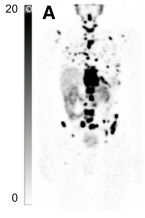

Fig. 3. A maximum intensity projection of [177Lu]Lu-PSMA-617 (SPECT/CT) of a patient with metastasised prostate cancer. Small black spots in the image are small tumour lesions. This is a partial SPECT/CT image from a study conducted by L. Emmett and co-workers, where the authors were investigating how to quantify SPECT data.43 The full research was originally published in JNM © SNMMI , and can be accessed via https://doi.org/10.2967/jnumed.122.264398.

Targeted radionuclide therapy (TRNT) using lutetium-177 conjugated to PSMA-617 (a pseudopeptide which binds to a prostate cancer biomarker called prostate specific membrane antigen, colloquially shortened to PSMA) has shown promise as a treatment for metastatic castration-resistant prostate cancer (mCRPC), particularly in patients who have undergone chemotherapy and received androgen receptor pathway inhibitors.44–47 [177Lu]Lu-PSMA-617 is favoured for its optimal half-life, cost-effectiveness, and beta emission, leading to its approval by the Food and Drug Administration (FDA) and the European Medicines Agency (EMA).46 Additionally, diagnostic variants (like gallium-68) of the same molecule are also available, making progression of the treatment much easier to follow.48 Clinical trials have demonstrated efficacy and safety, but a notable number of patients have no response to the treatment or experience disease progression after initial benefits.47,49–51 Alternative treatments are limited for these patients but this will soon change with an increase in clinical trials replacing 177Lu with newer, more potent radionuclides.